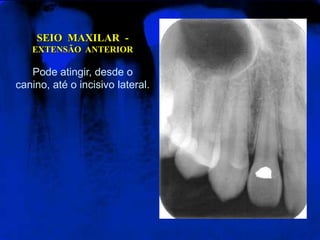

SEIO  MAXILAR  -  EXTENSÃO  ANTERIORPode atingir, desde o canino, até o incisivo lateral.